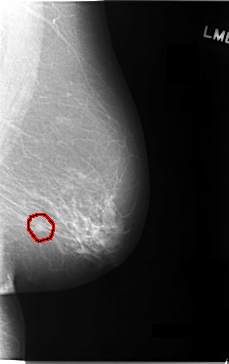

C_0027_1.LEFT_CC

LEFT_CC LINES 5840 PIXELS_PER_LINE 3696 BITS_PER_PIXEL 12 RESOLUTION 50 OVERLAY

FILE: C_0027_1.LEFT_CC.OVERLAY

TOTAL_ABNORMALITIES 1

ABNORMALITY 1

LESION_TYPE MASS SHAPE LOBULATED MARGINS MICROLOBULATED

ASSESSMENT 5

SUBTLETY 4

PATHOLOGY MALIGNANT

TOTAL_OUTLINES 1

BOUNDARY